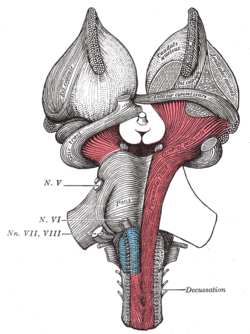

Deep dissection of brain-stem. Lateral view. Superficial dissection of brain-stem. Ventral view.

Superficial dissection of brain-stem. Ventral view. Coronal section of brain immediately in front of pons.

Genu

The genu is the flexure of the internal capsule. It is formed by fibers from the corticonuclear tracts. The fibers in this region are named the geniculate fibers; they originate in the motor part of the cerebral cortex and, after passing downward through the base of the cerebral peduncle with the cerebrospinal fibers, undergo decussation and end in the motor nuclei of the cranial nerves of the opposite side. It contains the corticobulbar tract, which carries upper motor neurons from the motor cortex to cranial nerve nuclei that mainly govern motion of striated muscle in the head and face.